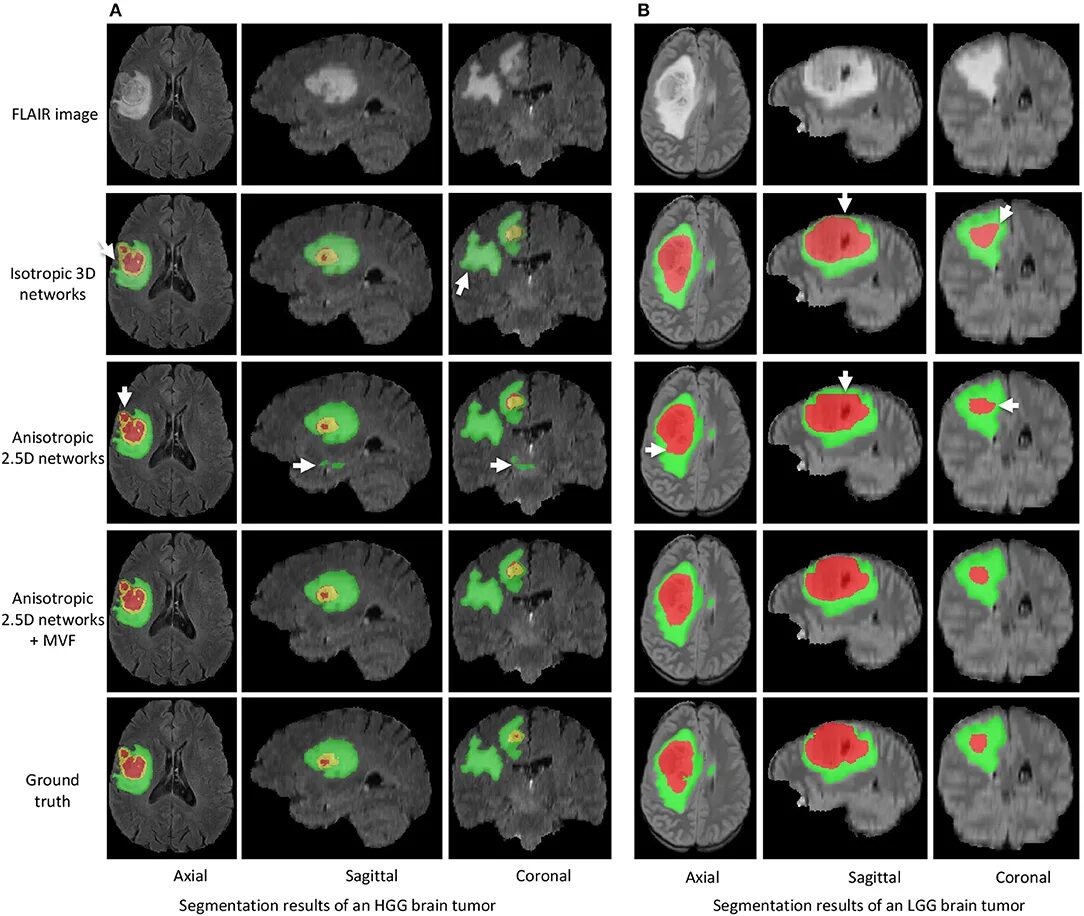

Сколько живут с доброкачественной опухолью головного мозга